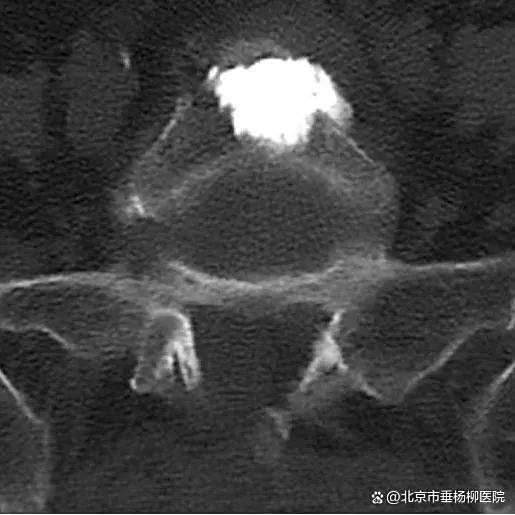

▲术后X线,椎体内骨水泥弥散良好

▲术后CT,椎管狭窄较前明显好转